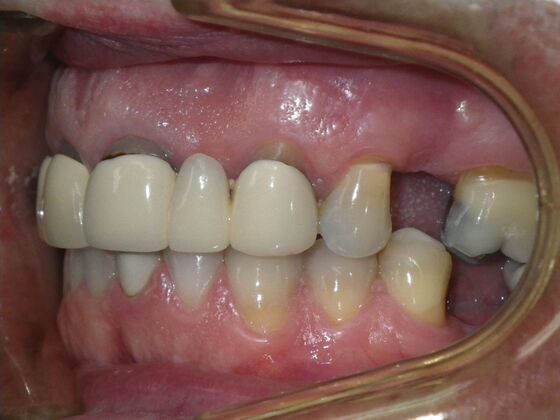

Cosmetic Changes with Veneers and Crown and Bridge: Case 5

Patient wanted to see about getting his upper front crowns replaced. He has had them for 35 plus years. Also concerns about his gums receding and the metal margins of crowns showing. Also talked with him about the need for crown lengthening which would have helped decrease the gummy smile; however, he chose not to do this. I thought just replacing the existing crowns to the existing gingival margins would be a great help. So the existing porcelain/metal crowns were removed and new all ceramic single unit crowns placed from upper right cuspid,lateral incisor and right central incisor. Then a 3-unit all ceramic bridge was placed from upper left central incisor to upper left cuspid. This patient and most of all his wife were very pleased with the end result.